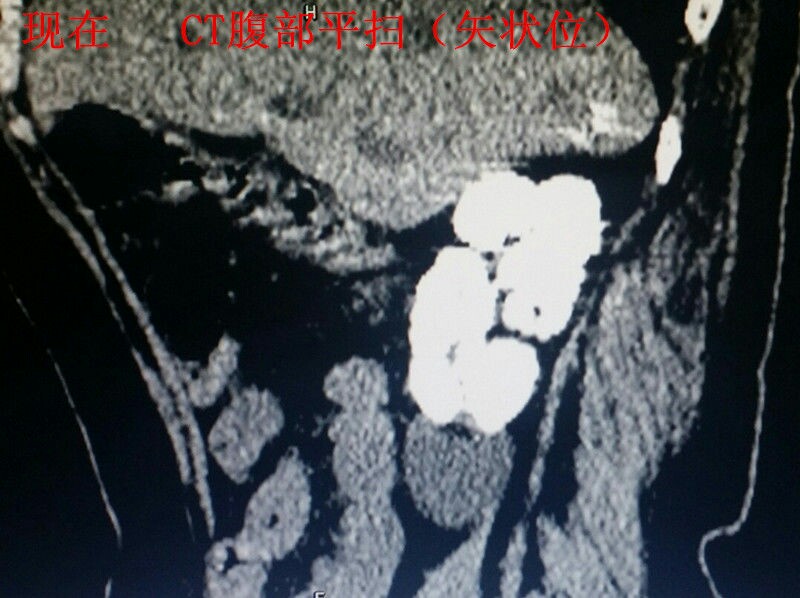

男性青年,未婚。 主诉:咳嗽数月,发现血尿三天。 现病史:患者半年前出现咳嗽症状,自服“消炎药”可减轻,一直未愈,近来加重。右腰背部偶感不适。发现终末血尿三天。患者自述近来消瘦、乏力。精神可,饮食可,睡眠好。 既往史:患者四年前因粟粒性肺结核就诊于当地结核病医院,给予口服抗结核治药物治疗(具体药物不详),后复查未见明显异常。 个人史:吸烟十年。 婚育史:未婚。 家族史:父母体健,无遗传病史。 实验室检查:肌酐:200umol/L(59-104) 尿素:10.4umol/L(2.86-8.2) 本院非结核病防治医院,无结核相关实验室检查。其余检查无阳性发现。 影像学检查(见插图): 1.四年前胸部平片及CT显示:双肺密布粟粒样结节,考虑肺结核。 2.现在胸部CT示:右肺尖及双肺背侧可见片状不规则高密度影,右肺中叶见厚壁空洞。考虑空洞型肺结核。 3.现在行腹部立位平片及CT示:右肾呈高密度团块状,结合病史考虑肾自截。 4.为进一步明确分肾功能,行核素肾动态显像示:右肾未见明显血流灌注,右肾未见明显显影,右肾功能重度受损,右肾肾图呈低水平延长线性改变。左肾功能大致正常。 诊疗经过:鉴于右肾无功能,行右肾摘除术(送病理,回报:肾结核)。请胸外科会诊,建议转入胸外科行肺段切除术。目前右肾摘除术后。 小结:近年来结核病例有上升趋势,尤其是肺结核。本病例类似的情况较少见,特此分享供大家学习。